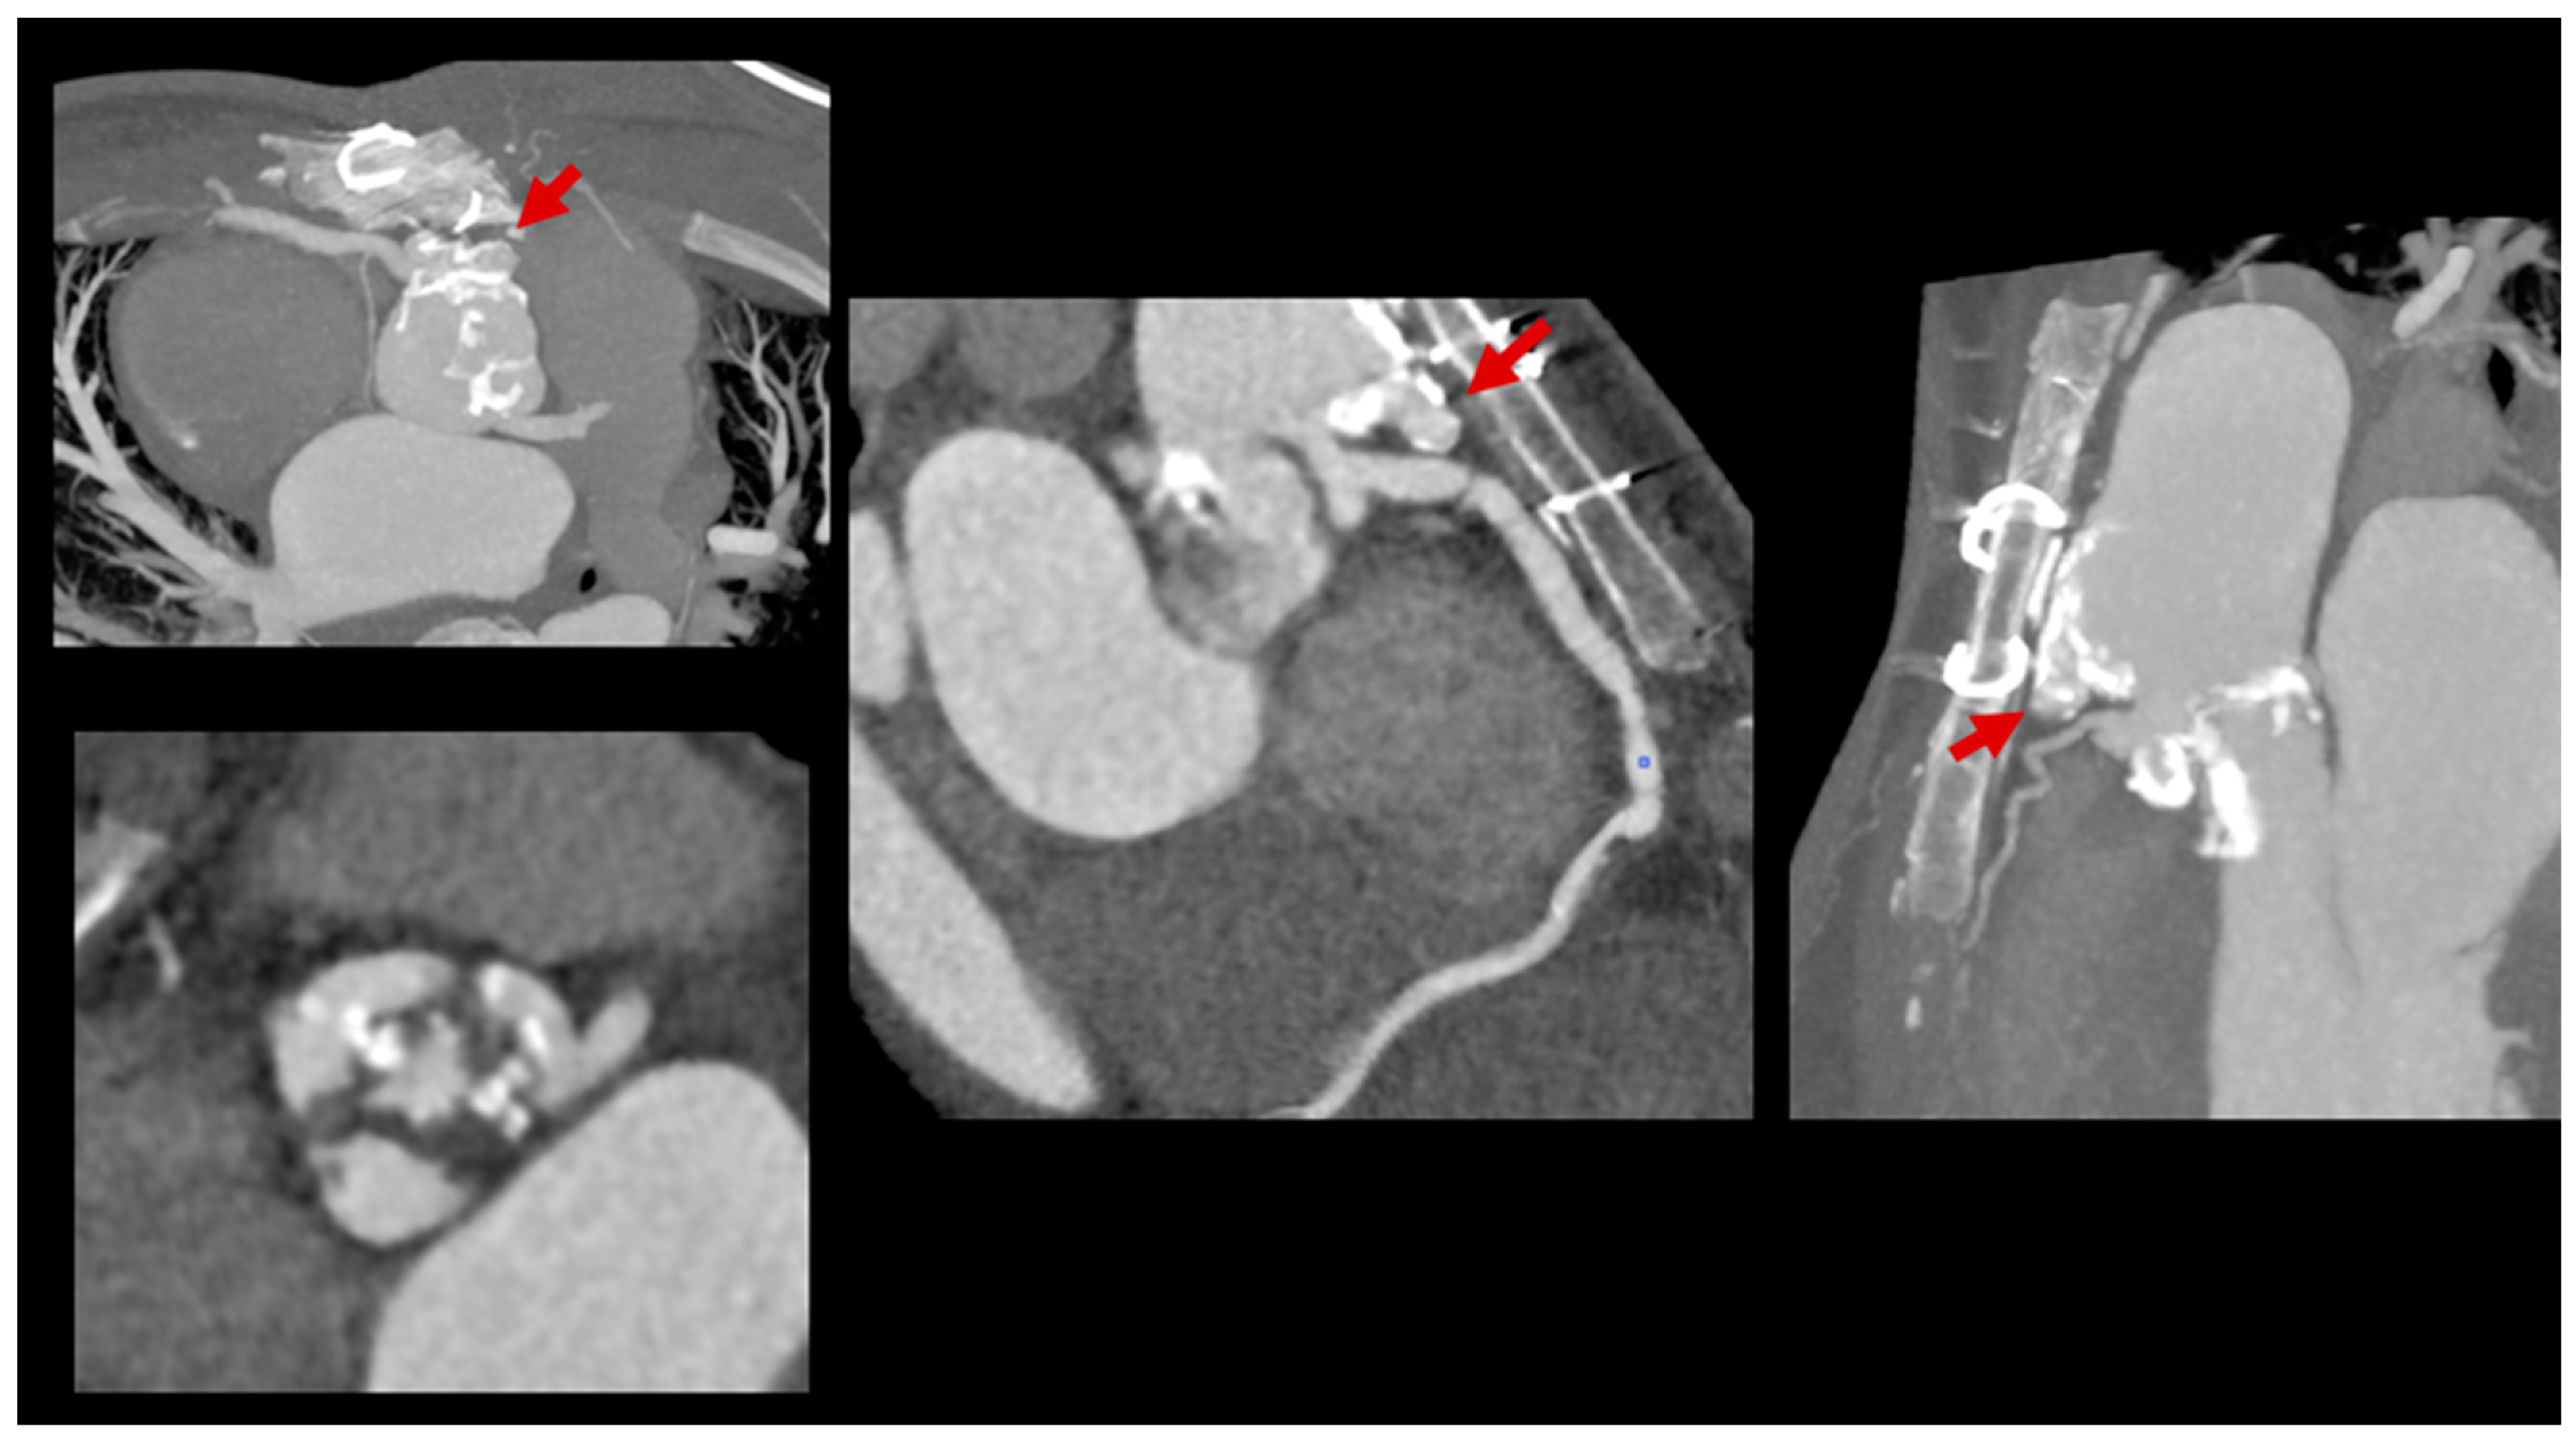

3.3. Role of Cardiac Computed Tomography

- Detecting Device-Related Infections: PET/CT is highly effective for evaluating infections involving prosthetic valves, pacemaker leads, and other intracardiac devices (Figure 7). It offers unmatched sensitivity in visualizing device pockets and lead tracks, helping differentiate sterile thrombi from infectious vegetations. This is critical in CHD patients, who frequently require surgical implants as part of their treatment.

- Integration with CT Angiography (PET/CTA): When PET is paired with CT angiography, the resulting hybrid imaging achieves remarkable diagnostic precision. This combination leverages PET’s sensitivity for detecting metabolic activity in infected tissues and CTA’s detailed visualization of structural abnormalities. For instance, PET/CTA achieves a sensitivity of 91% and a positive predictive value of 93% for diagnosing infections involving prosthetic valves and intracardiac devices, significantly enhancing diagnostic confidence [99].